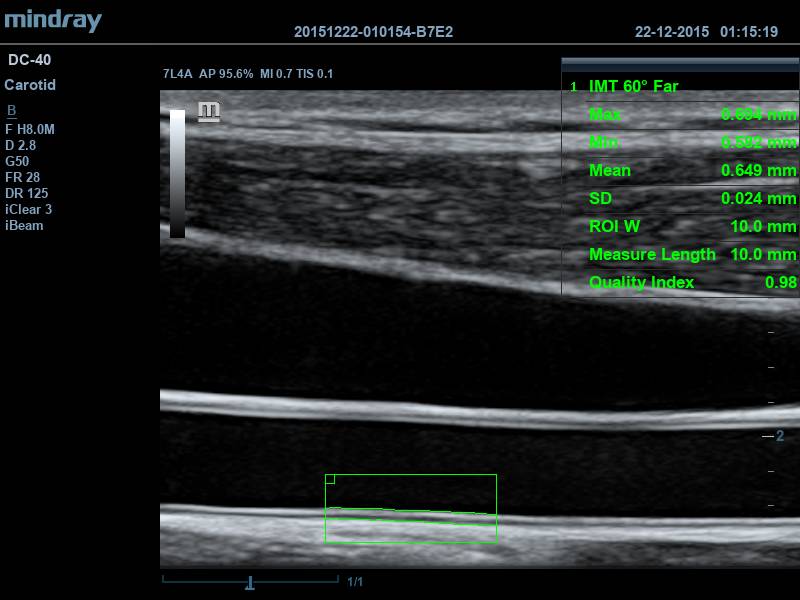

• Auto IMT Package Программное обеспечение для автоматического измерения толщины комплекса интима-медиа

• Программное обеспечение для автоматического измерения толщины комплекса интима-медиа Программное обеспечение для оценки эластичности ткани методом компрессионной эластографии(поддерживается на датчиках 7L4A, L12-3E and L14-6NE)